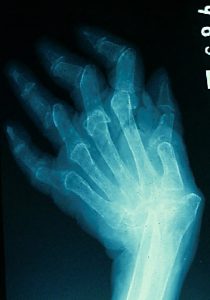

术前(左)和术后(右)关节X光图片病人三年来第一次外出手术